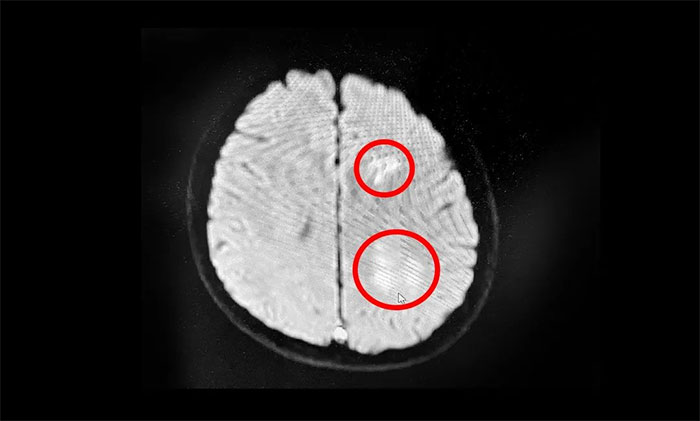

▲MR提示:左侧额顶叶多发(静脉性)脑梗塞